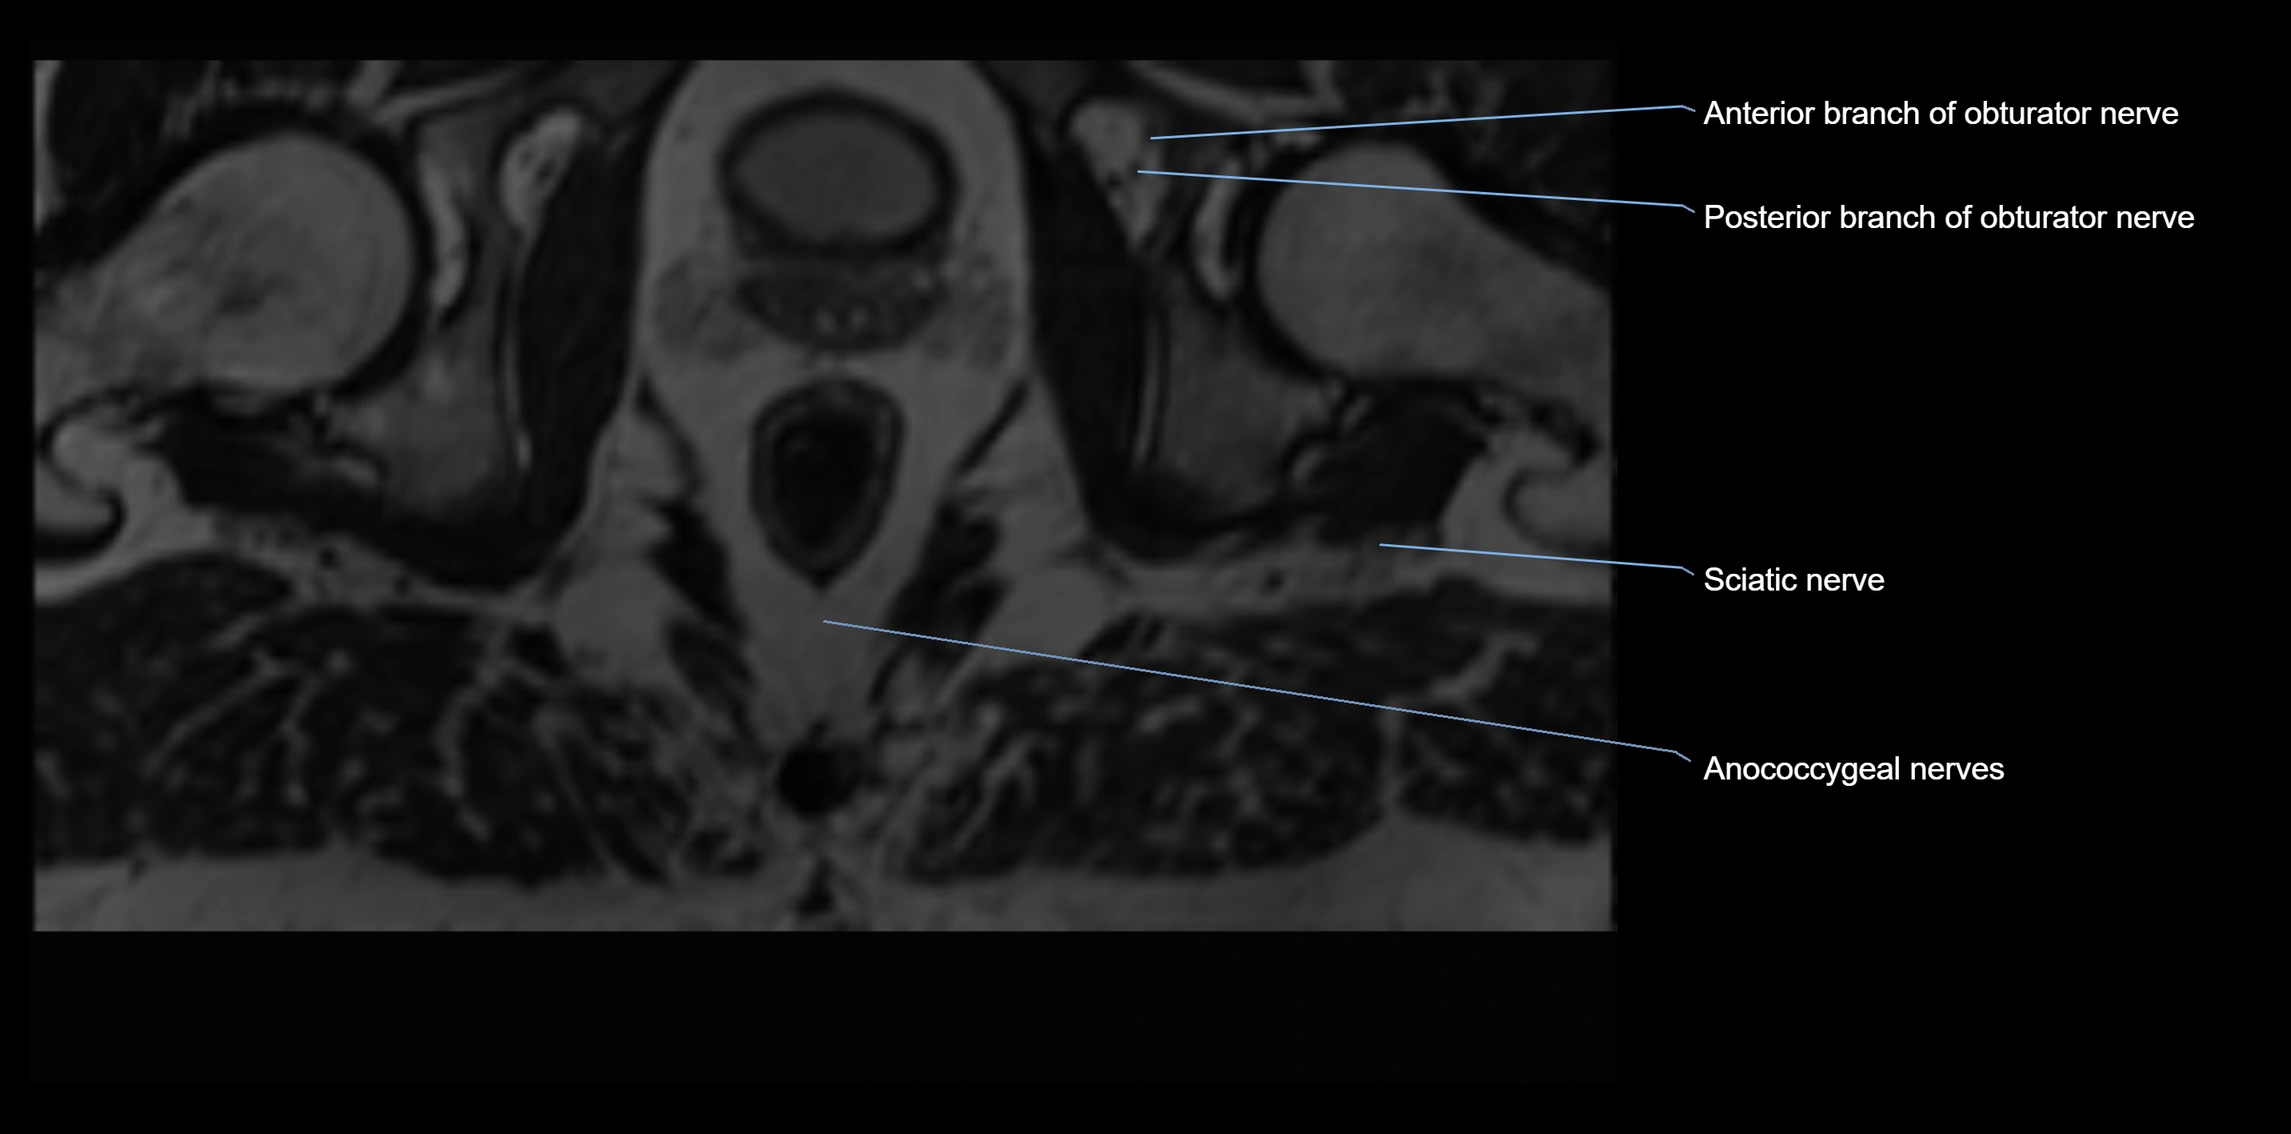

Anococcygeal nerve

The anococcygeal nerve is a small sensory nerve derived from the coccygeal plexus, which itself is formed by the ventral rami of S4, S5, and the coccygeal nerve (Co1). Although tiny, this nerve plays an important role in supplying the skin of the coccyx and the area between the anus and coccyx. It passes through the sacrotuberous ligament and runs in the midline behind the coccyx.

Despite its small size, the anococcygeal nerve is clinically important because of its involvement in coccygodynia (coccyx pain) and perineal pain syndromes.